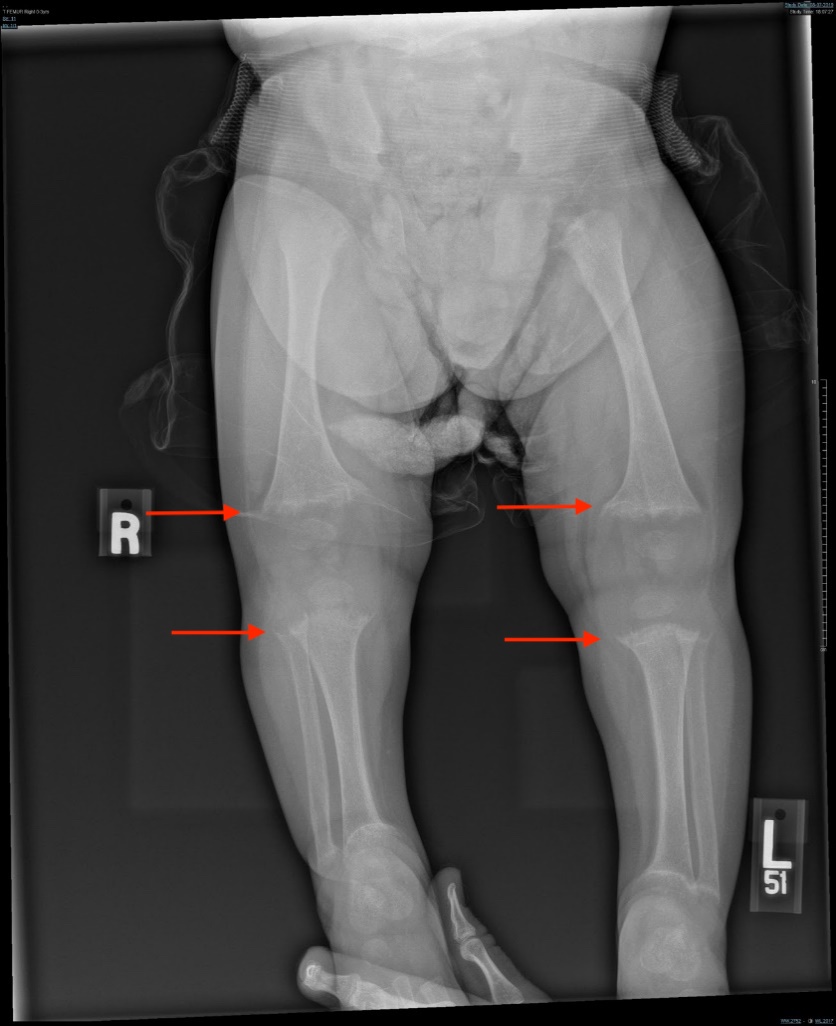

A radiologic skeletal survey demonstrated abnormal bone mineralization, fraying, splaying, and cupping of numerous sites bilaterally (femora, tibiae, fibulae, radii, ulnae). There was also mild expansion of the anterior rib ends at the costochondral junction bilaterally (Figures 1-4).

Figure 4. Radiologic skeletal survey demonstrated fraying, splaying, and cupping of the femora, tibiae, and fibulae bilaterally (arrows).